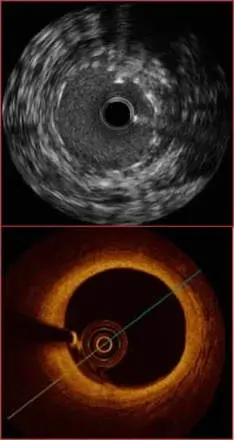

Intravascular ultrasound (IVUS) and Optical coherence tomography (OCT) accurately assess the structure of one or more of the heart arteries. These tests help identify any underlying disease that may be present. This can be done during a coronary angiogram to understand any disease seen on angiogram, but can also be used to accurately assess the health of an old stent or can be used to optimize the insertion of a new stent. As the name suggests, IVUS is an ultrasound based test that involves the passage of a thin probe into an artery which allows its internal structure to be visualised. OCT is a light detecting probe technique that gives a much better resolution and a clear picture of the internal structure of an artery. When intravascular imaging is required, the choice between these tests is dependent on a number factors including a variety of clinical factors and also the heart disease in question.